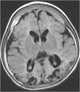

Osteopetrosis infantile form with nervous system involvement

Infantile osteopetrosis